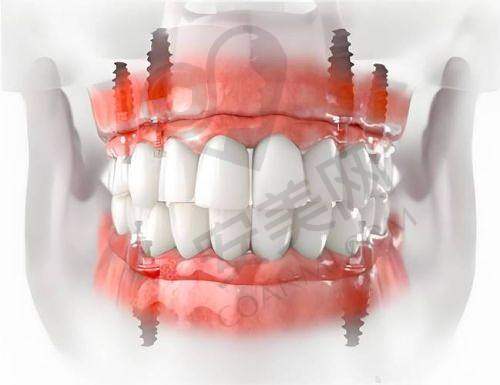

韩国neo种植牙具有诸多优势。首先,它的材料质量可靠。采用了精良的生物材料,与人体组织的相容性好,能够更好地与牙槽骨结合,提高种植的成功几率。其次,neo种植牙的设计合理,模拟了自然牙齿的形态和功能,能够修复良好的咀嚼功能。在外观上,也与自然牙齿非常相似,几乎看不出是种植牙。此外,韩国neo种植牙的研发和生产技术成熟,经过了大量的临床验证,具有较高的稳定性和耐用性。患者在使用过程中,不用担心出现松动、脱落等问题,可以长期保持良好的使用成效。

与其他品牌的种植牙相比,韩国neo种植牙具有独特的优势。在价格方面,韩国neo种植牙相对较为亲民,尤其是济南可恩口腔推出的2899元起的价格,对于特别多患者来说是一个不错的选择。在技术上,neo种植牙不断创新和改进,其表面处理技术能够更好地促进骨结合。而且,韩国的口腔产业发展快速,neo种植牙的研发和生产能够紧跟国内外潮流。在临床应用方面,neo种植牙已经有了大量的成功实例,证明了其可靠性和有效性。此外,韩国neo种植牙的适配性好,能够与多种牙冠材料搭配,满足不同患者的需求。